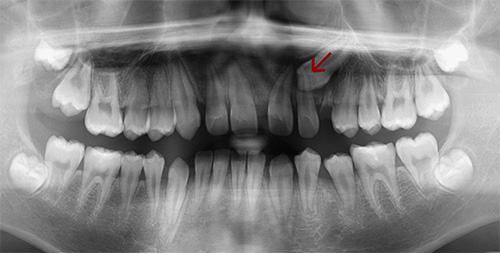

Orthodontic Treatment X-ray - Before

After Series of Teeth Extractions, Upper Left Canine Unerupted.

Ready to Start Ortho Treatment